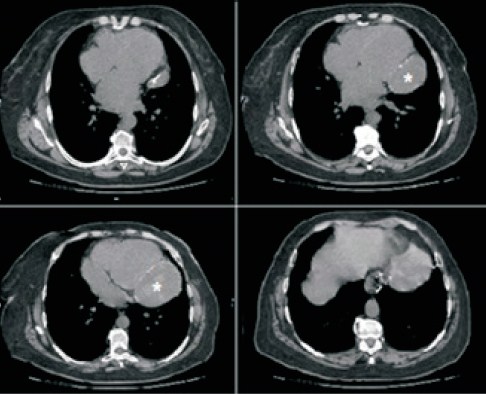

Luego, se realiza tomografía de tórax (figura 3), que describe una imagen compatible con un tumor mediastinal izquierdo en relación con el sector posterolateral izquierdo de la silueta cardíaca, masa sólida, heterogénea, con áreas hipodensas, de 92 x 79 x 72 mm en sus diámetros anteroposterior, transversal y longitudinal. En la periferia, en relación con el pericardio parietal, se ven calcificaciones laminares, sin realce con contraste. En el sector retrocardíaco por dentro de la imagen descrita, se ve el tubo gástrico de la cirugía bariátrica referida con las imágenes de alta densidad, características de la sutura mecánica.

Figura 3: Tomografía computada de tórax ventana mediastinal: se observa en relación posterolateral al ventrículo izquierdo masa sólida heterogénea. * Masa sólida.